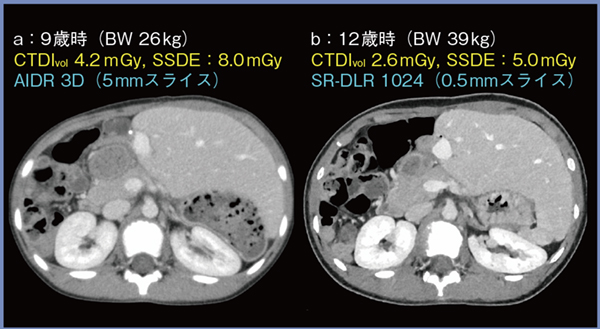

SR-DLR 1024では,小児の微小な構造も鮮明に描出されるため,急性腹症や腫瘍性病変,先天性奇形などのさまざまな疾患において有用性があると考える。症例3は,先天性胆道閉鎖症にて生体肝移植後の女児である。9歳時に撮影されたCTDIvol:4.2mGy,AIDR 3D,5mmスライス厚の画像(図5 a)に対し,12歳時に撮影されたCTDIvol:2.6mGy,SR-DLR 1024,0.5mmスライス厚の画像(b)は,被ばく線量が約4割低減され,スライス厚は1/10であるにもかかわらず,低ノイズが維持され,面内および体軸方向の解像度向上を生かした詳細な評価が可能であった。

図5 症例3:先天性胆道閉鎖症にて生体肝移植後の女児